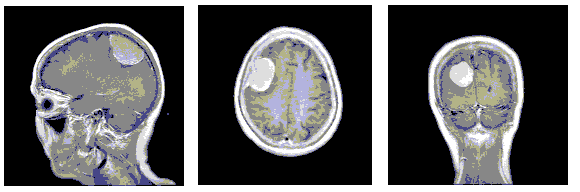

Refer to caption

Figure 2: Brain MRI slices captured from different directions [6]

This brain tumor T1-Weighted MRI image-dataset consists of 3064 slices. There are 1047 coronal images. Coronal images are those which are captured from the back of the head. Axial images, those taken from above the skull, are 990 in number. The dataset also contains 1027 sagittal images that are captured from the side of the skull. This dataset has a label for each image, identifying the type of the tumor. These 3064 images belong to 233 patients. The size of each image is 512*512 pixels. The dataset includes three types of tumors- 708 Meningiomas, 1426 Gliomas, and 930 Pituitary tumors, which are publicly available: here